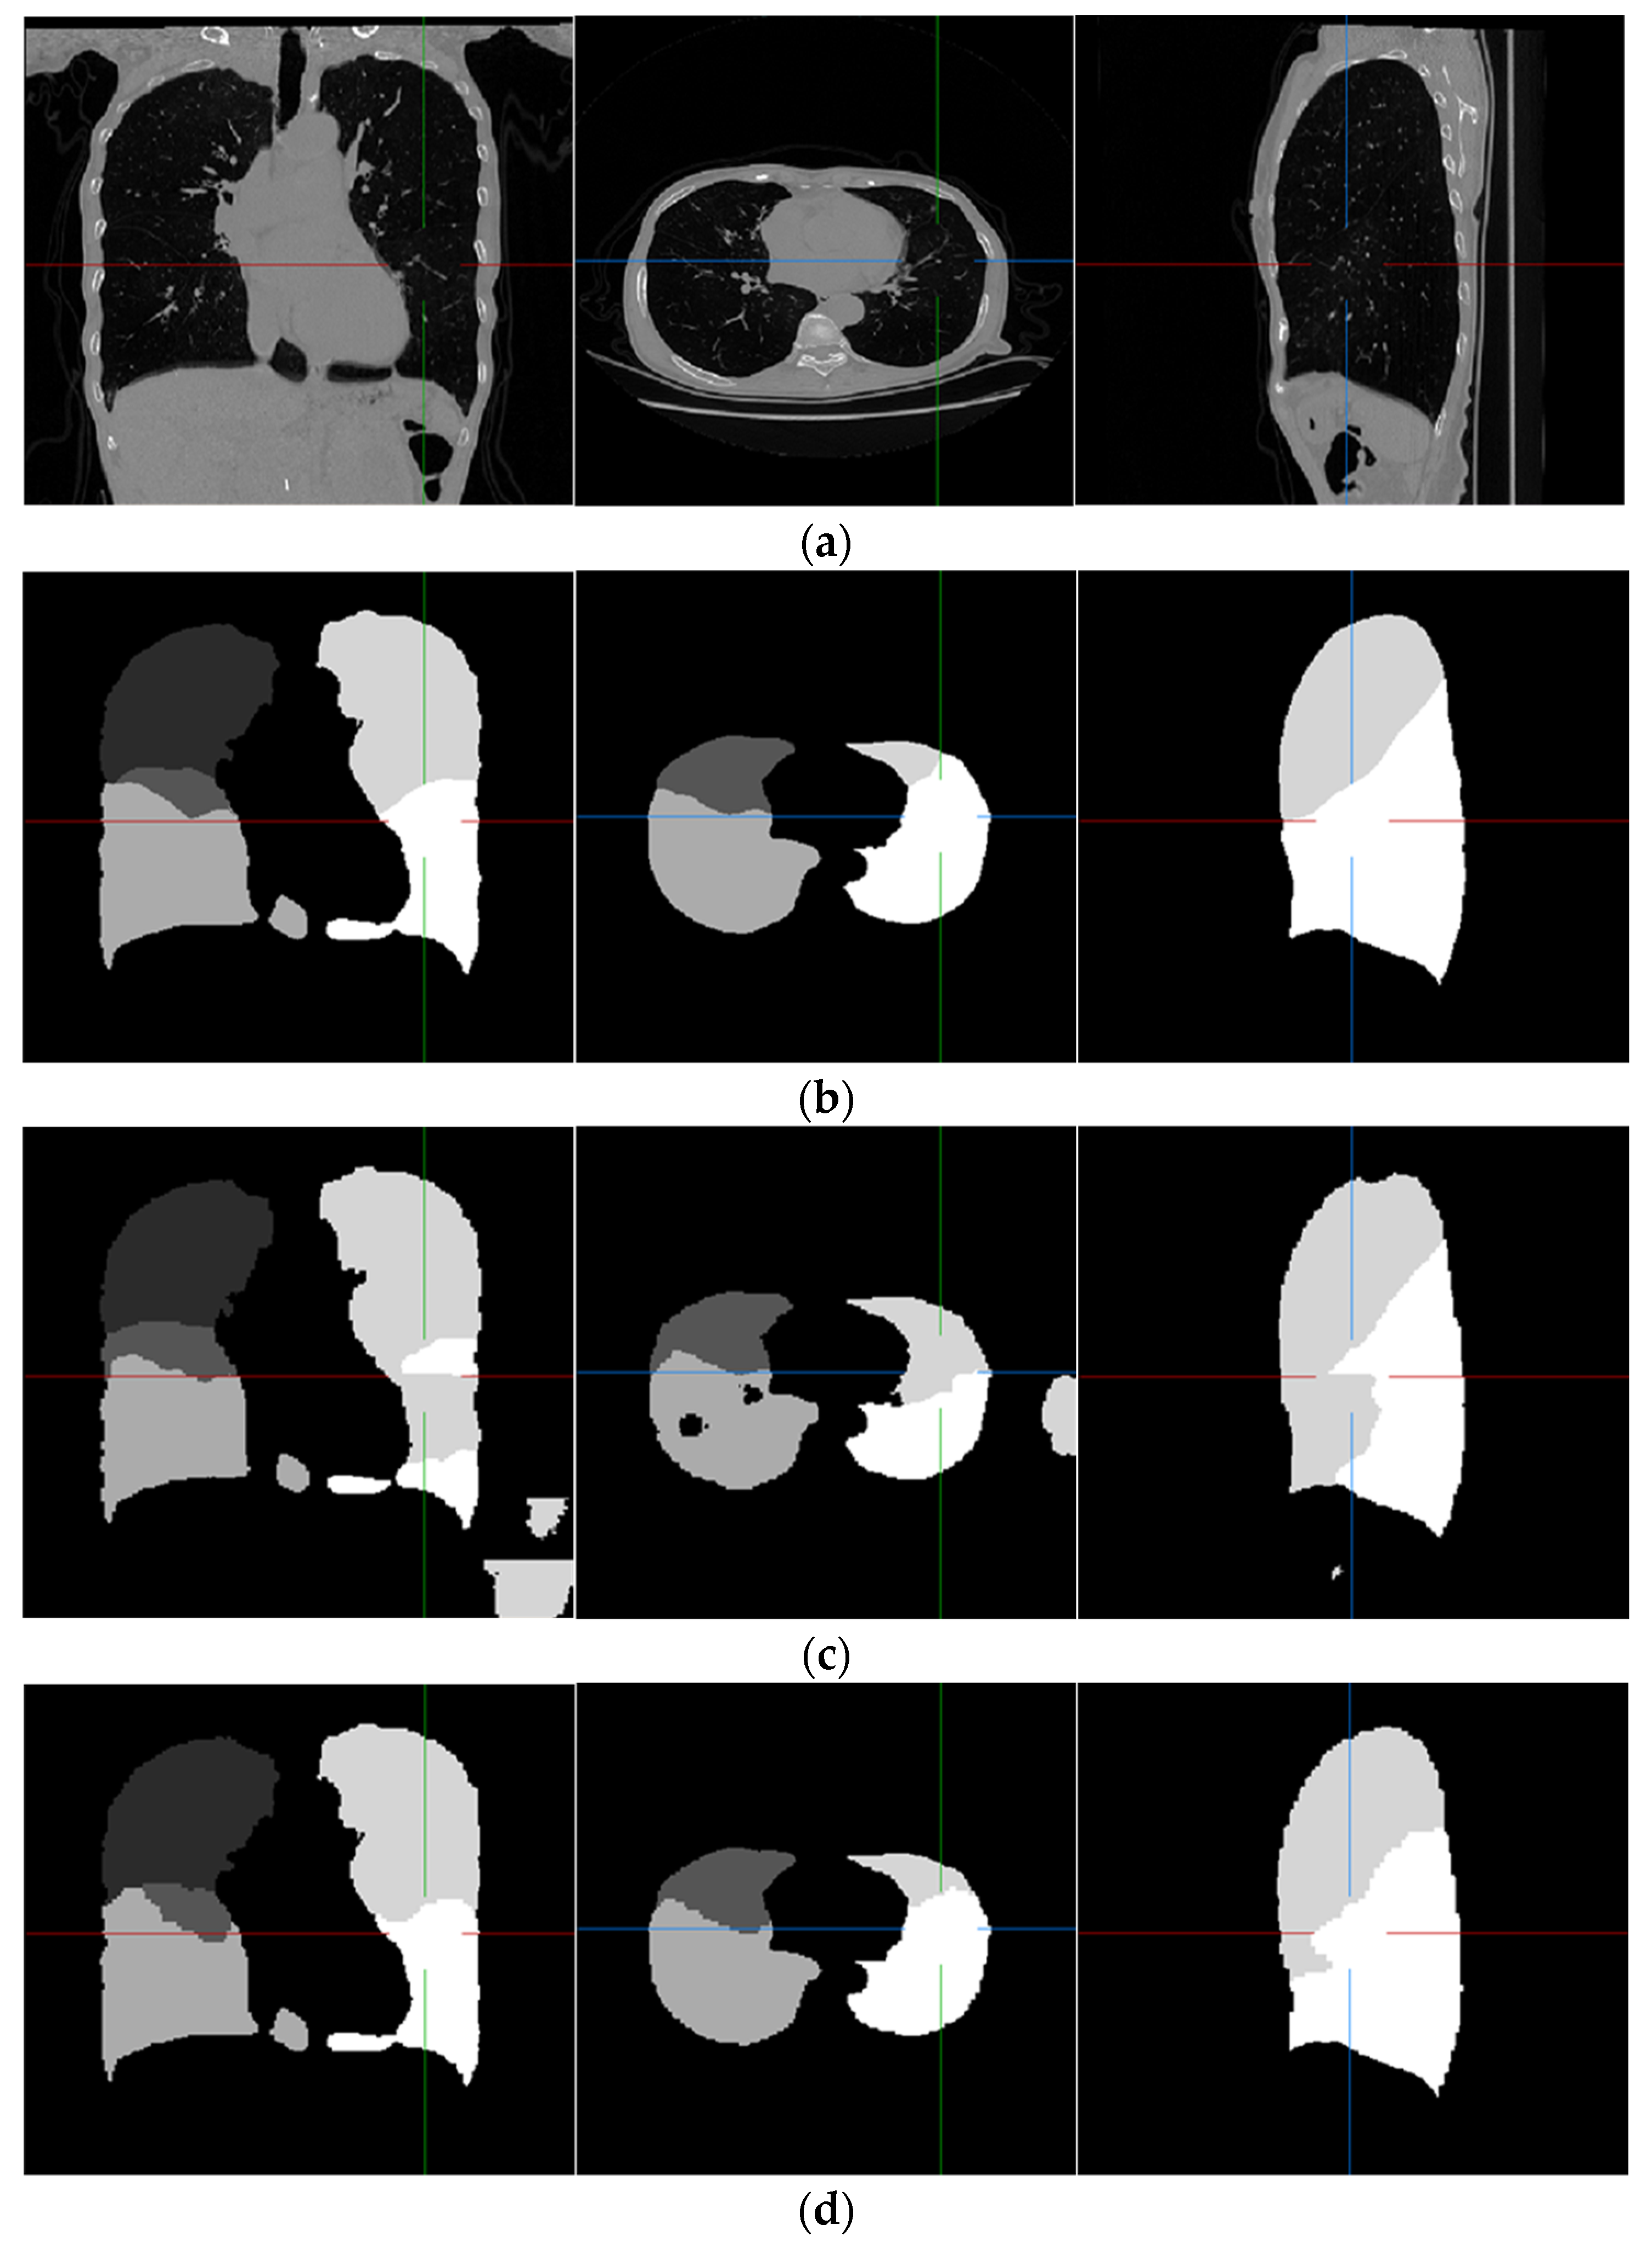

Examples of pulmonary lobe segmentation are shown in Figure 4 and Figure 5 for qualitative visualization. In Figure 4, a case with a general morphology of the lung is presented. In Figure 5, a case with morphological specificity is selected.

Figure 4.

An example of the results of the experiment. (a) Original scan; (b) ground-truth; (c) FRV-Net; and (d) proposed method.

From Figure 4 and Figure 5, it is easy to observe that the results of the FRV-Net are interfered with by the false identification in the background. Additionally, there are irrational holes in the segmented lobe of the FRV-Net. Figure 4 shows that the proposed method could obtain a comparable segmentation result with the FRV-Net method. While in cases with large anatomical differences in the training dataset, the proposed method could avoid a wide range of misclassifications, owning to the aid of the fissures (see Figure 5).

The quantitative evaluation is expressed in Table 3. The results of the FRV-Net are further processed by masking the background voxels for a fair comparison, which is recorded as the revised FRV-Net method.

The dice coefficient of the revised FRV-Net method is significantly improved for the left upper lobe. Even compared with the revised FRV-Net method, the result of the proposed method is competitive. Furthermore, the proposed method could prevent interference from the pathological changes in morphology and avoid unreasonable holes in the segmented lobes. Generally, the proposed method could segment the pulmonary lobes accurately and robustly.